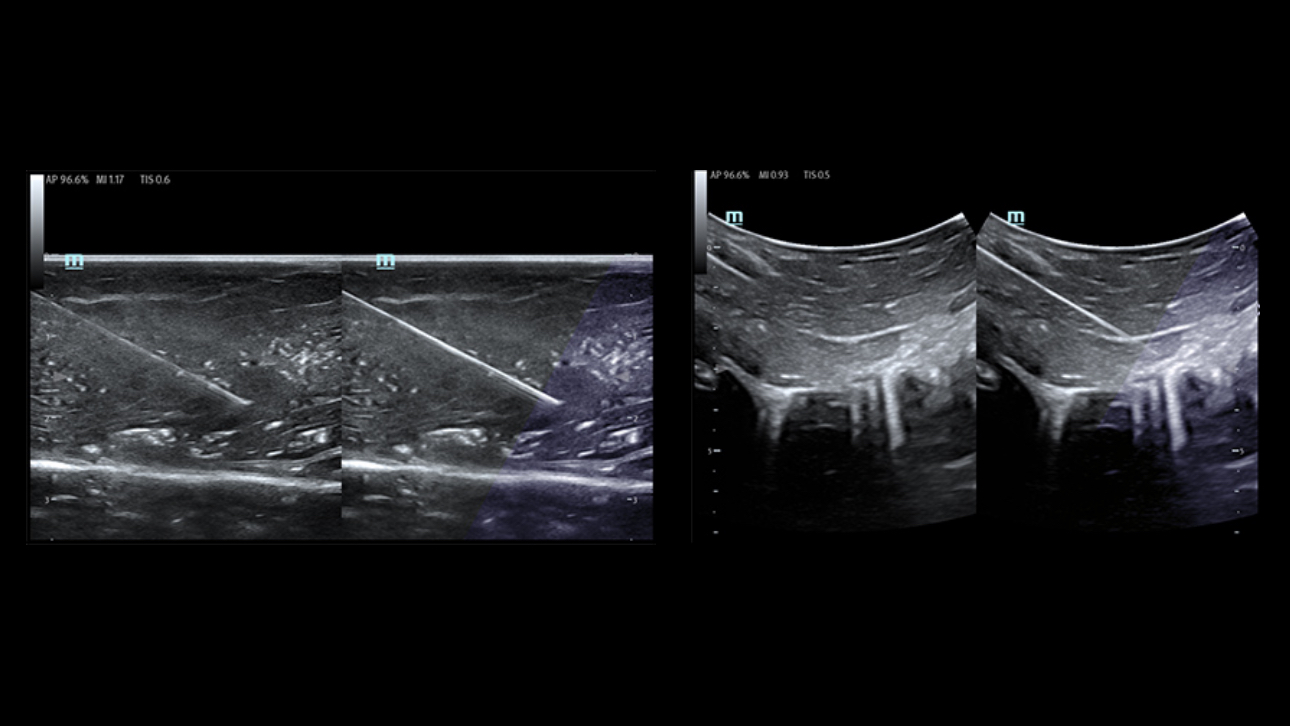

X-Pilot: Clinical Application-Oriented Workflow

Based on the professional society guidelines for point of care ultrasound, the X-Pilot suite integrates historical diagnostic images and multi-organ data into a concise and precise view of the patient status to support rapid clinical decisions at the bedside.